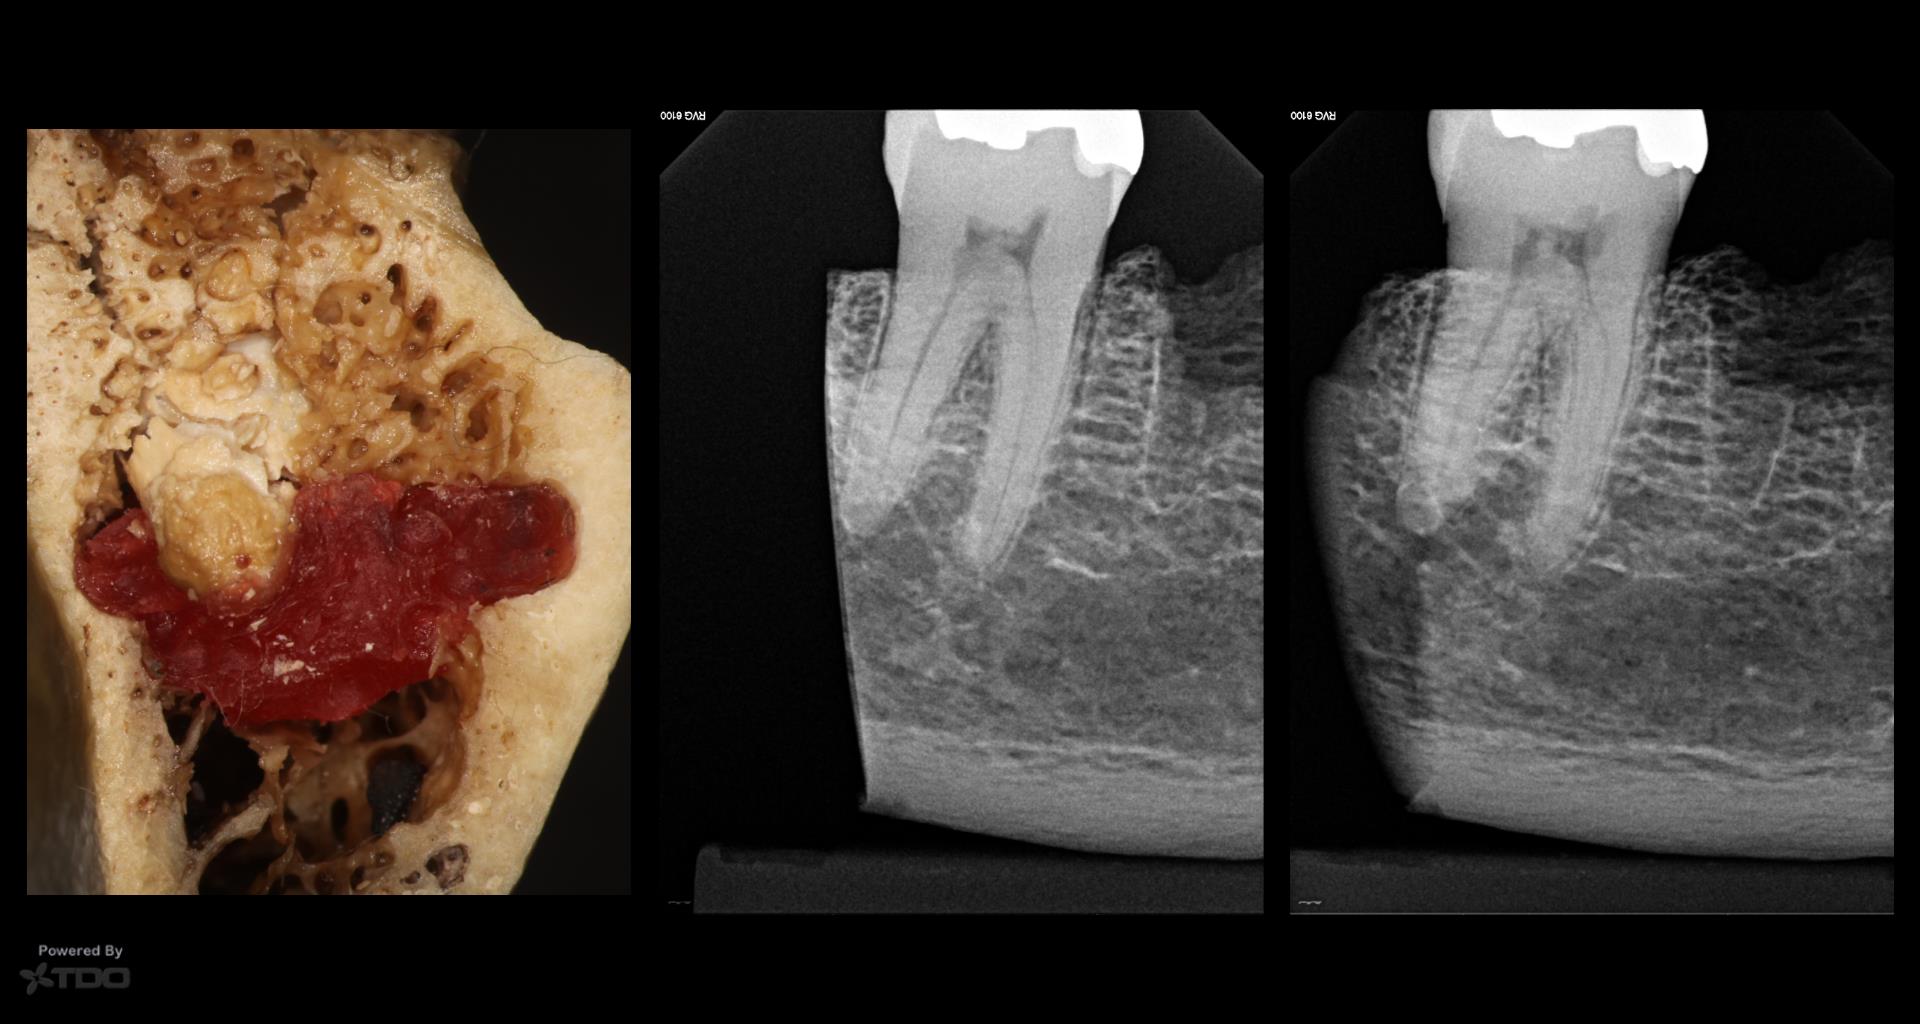

The discussion with James brought back memories of our original PERF CBCT project (that actually launched the CBCT revolution in endodontics, although no one gives us credit for that). Carlos Murgel, Peter Endo and I compared standard PA and CBCT imaging in many different ways. Standardizing the PA radiography was critical and proved to be a challenge. Carlos came up with several methods that finally allowed us to duplicate angles within 1-2 degreess. It was a lot of work…. gbc